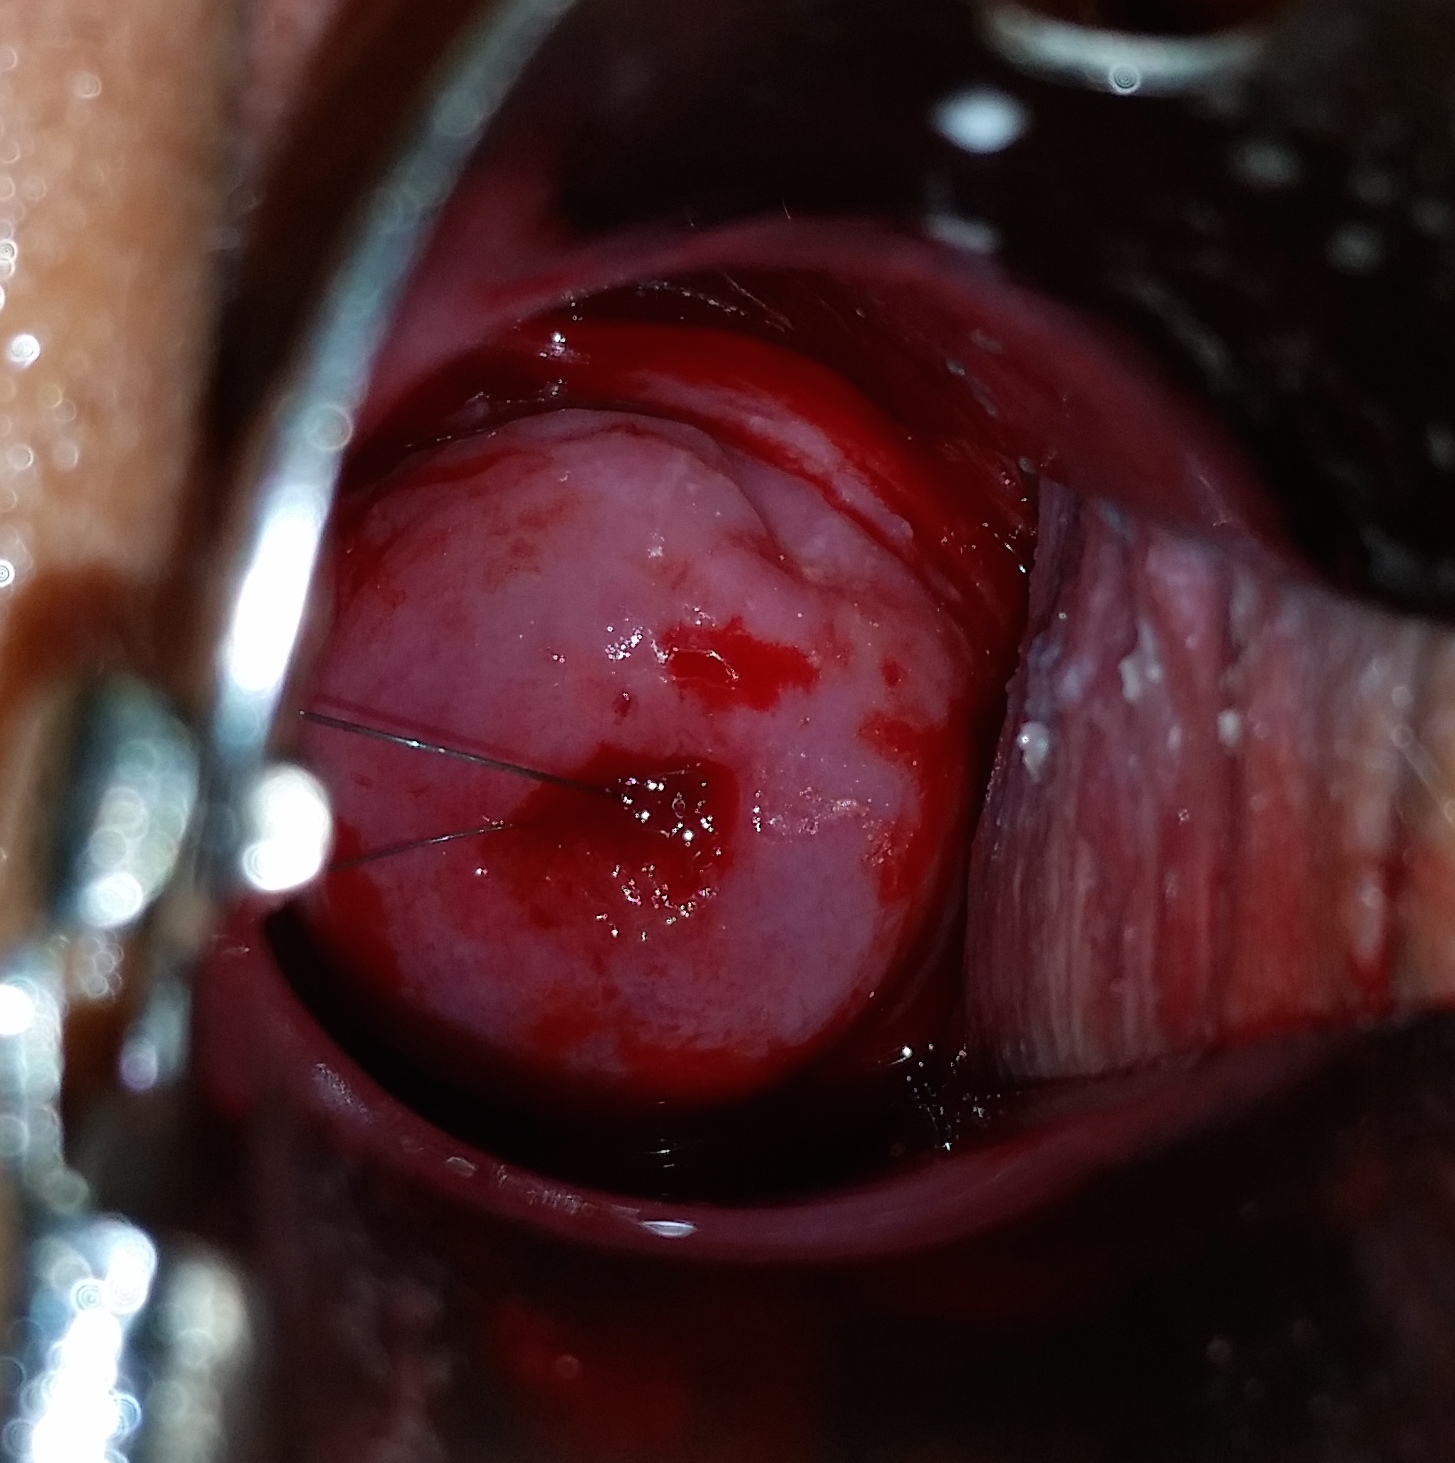

5. 삽입 및 제거

IUD 삽입 및 제거는 의료 전문가(한국에서는 산부인과 의사)가 시행한다.[95] 삽입 시 통증 완화를 위해 국소 리도카인을 사용할 수 있다.[170] 삽입 절차는 보통 5-10분 정도 소요되며,[172] 질경을 사용하여 자궁경부를 확인하고, 삽입기를 통해 IUD를 자궁 내에 위치시킨다.[171]

제거는 삽입보다 간단하며, IUD에 연결된 실을 잡아당겨 제거한다.[107]